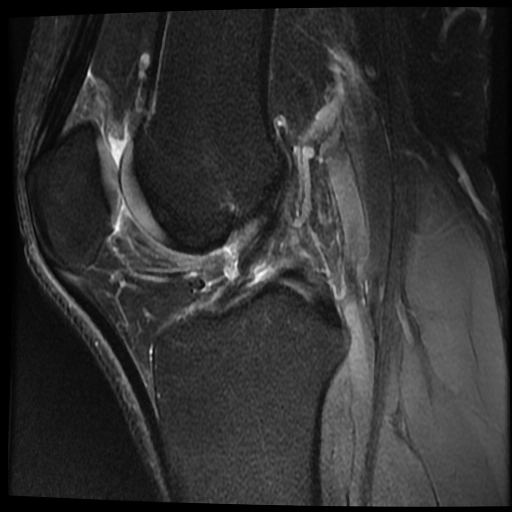

Rách dây chằng chéo trước ACL (Anterior cruciate ligament tear)

Rách dây chằng chéo trước (ACL) mạn tính